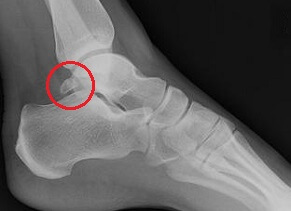

An extra piece of bone that gets stuck in the ankle when walking or pointing the foot

Causes: Bone fails to fuse in childhood and becomes symptomatic due to repetitive toe pointing movements or ankle injuries

Symptoms: Pain, swelling, tenderness and hard lump by achilles tendon

Full Article: Os Trigonum Syndrome